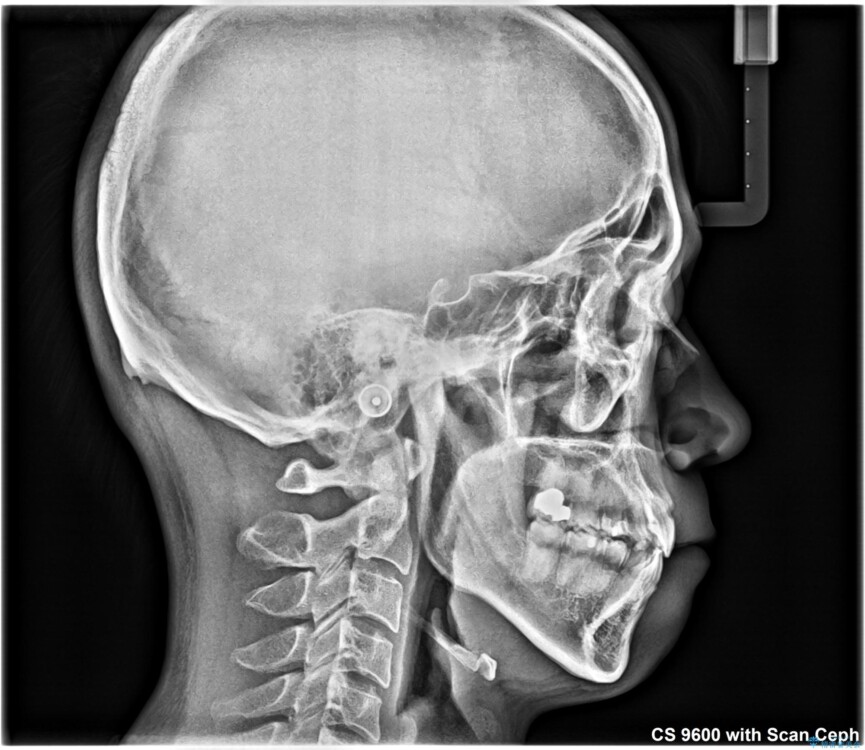

治療後について

八重歯はきれいに整い、前歯もバランスよく収まり、横顔のラインも自然に改善されました。

治療後、患者様は「思い切り笑えるようになった」と大変喜んでくださいました。

治療後

• 八重歯と前歯のガタガタを抜歯矯正で治療|クリアブラケット使用例 治療後画像